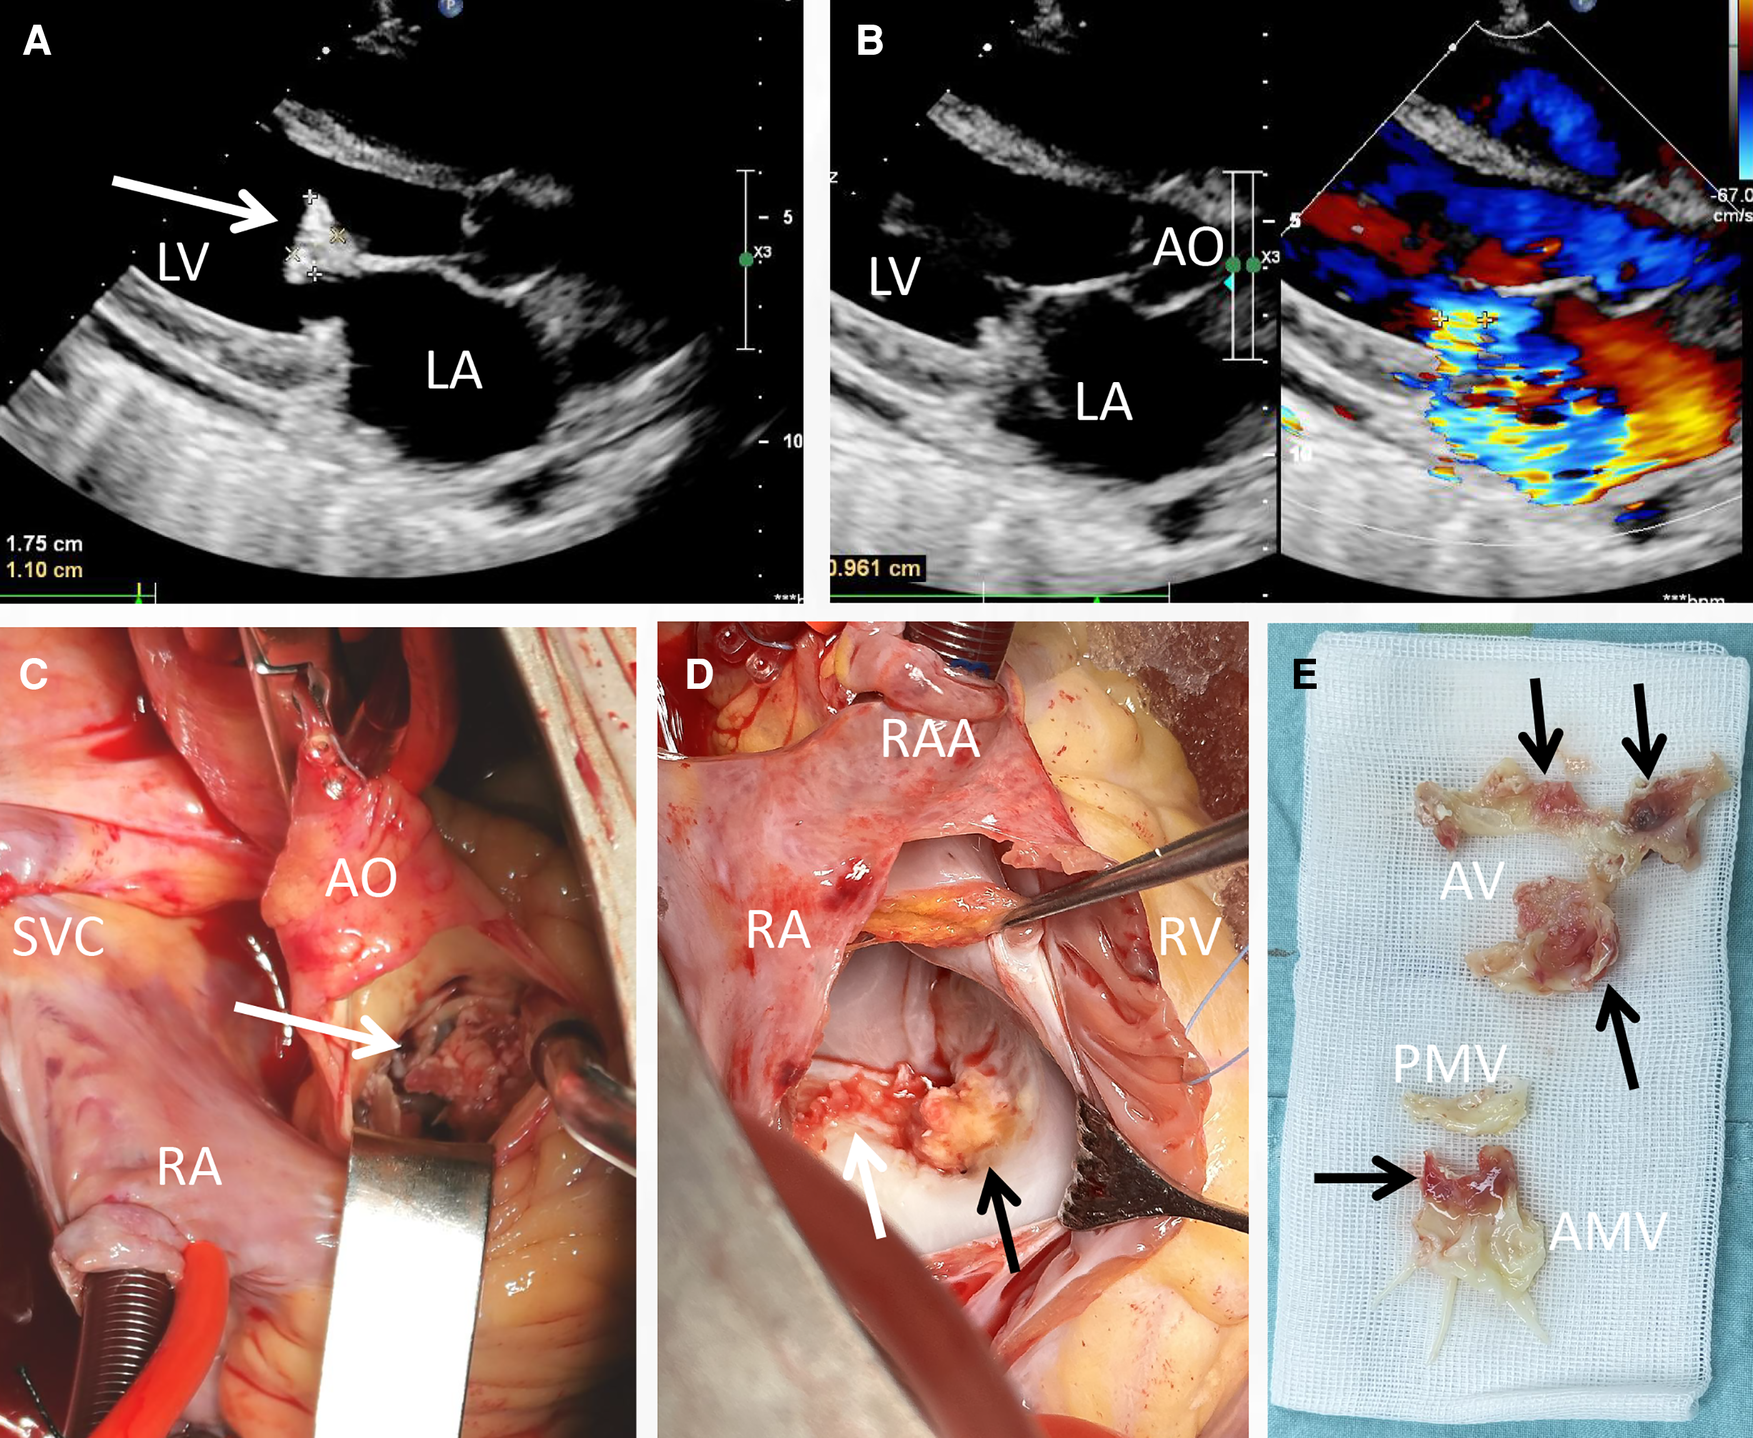

Laboratory investigations, including routine blood tests, unveiled a leukocyte count of 1.91 × 109/L, with an absolute neutrophil count of 1.08 × 109/L. Hemoglobin levels were measured at 88 g/L, NT-proBNP at 2,697 pg/ml, C reactive protein at 27 mg/L and the erythrocyte sedimentation rate at 53 mm/h. The (1,3)-β-d-glucan (BDG) and galactomannan (GM) tests were both detected positive. During physical examination, a pronounced precordial murmur was discernible during both systole and diastole. Notably, the chest radiograph did not exhibit significant signs of abnormality, except for a mild enlargement of the cardiac silhouette. Transthoracic echocardiogram (TTE) assessment (on the day of admission and 1 day before the operation) unveiled numerous echogenic vegetations affixed to the anterior mitral valve, including one particularly prominent vegetation measuring 17 × 11 mm (Figure 1A, arrow). This echocardiogram also indicated severe mitral insufficiency (Figure 1B). No embolic lesions were detected in both the cranial CT scanning and abdominal echography.

Figure 1

Transthoracic echocardiogram and intraoperative view of the vegetations. A vegetation sizing 1.75 cm × 1.10 cm (A, arrow), as well as severe mitral regurgitation (B) were detected pre-operatively; the yellowish vegetation (arrow) was observed intra-operatively with the infiltration of aortic valve (C), anterior mitral cusp (D) and mitral annulus (E).

Based on the findings from echocardiography, the BDG test and GM test results, the diagnosis of fungal endocarditis was strongly considered according to the DUKE criteria. A further detection though transesophageal echography was refused by the patient. Consequently, a valve replacement procedure was undertaken (1 day after the admission). Direct intracardiac surgery was conducted through a median sternotomy, with extracorporeal circulation routinely established through aortic, superior vena cava, and inferior vena cava cannulation at a mild hypothermia of 30°C. During the operation, additional small vegetations were detected on the aortic valve (2–4 mm in diameter), along with perforation (3 mm in diameter) of the valve cusp (Figure 1C, arrow). The infective valvular vegetation, displaying a yellowish hue, was approached via the ascending aorta (Figure 1C) and interatrial septum (Figure 1D). The vegetation was successfully excised (Figure 1E), and subsequent replacement with two mechanical valves (Sorin, sizing 25 mm and 27 mm for aortic and mitral valves, respectively) was carried out. The operation and postoperative recovery proceeded without complications. The post-operative data including blood routine and myocardial zymology were shown in supplement Tables 1, 2. The symptoms including the fever and persistent chest distress were not found post-operatively.